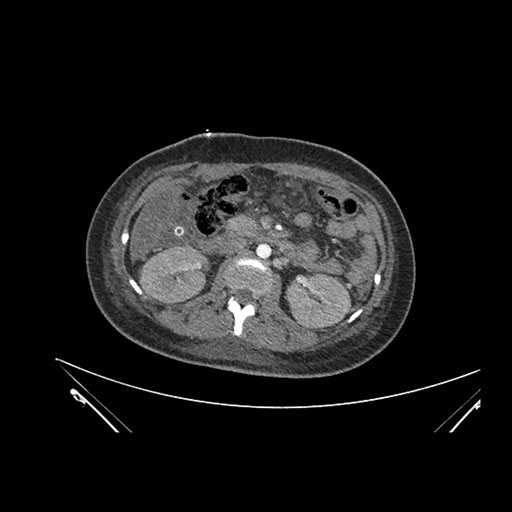

Axial Venous